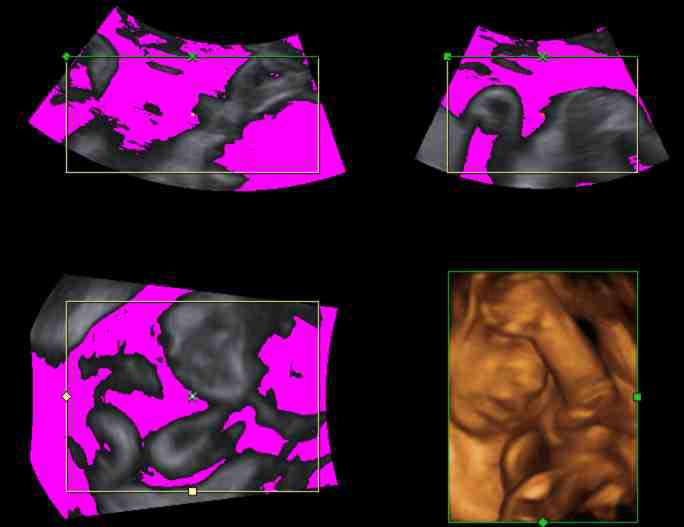

To increase robustness of the ultrasound segmentation, the various approaches are usually tailored for specific anatomies. Carneiro et al. have developed an automatic technique for segmenting the brain of a fetus carneiro08 . By first detecting the cerebellum, the system can narrow down the search for other features. On the other hand, segmentation is an extremely critical procedure which may obscure diagnostically relevant aspects of the anatomy under examination. Consequently, fully automatic segmentation techniques have not been implemented in clinical systems so far, with the exception of a method for follicle volumetry deutch09 , as shown in figure 3.

A great challenge with ultrasound segmentation is that the data is dependent on many factors. For one, different positions and orientations of the probe, while looking at the same anatomical part, can provide very different images. Hyper-echoic regions cast shadows onto the tissue behind it according to the probe position. This alone, makes ultrasound segmentation data highly uncertain. Most segmentation techniques return a model with no indication of the uncertainty of the result. To compensate for the fuzzy nature of the ultrasound data, Petersch et al. developed a soft segmentation technique for 3D ultrasound data petersch06 . This technique calculate a probability map for 3D ultrasound data, which in turn can be used to create soft representations of the features extracted.

4.1 Clipping

Feature extraction can be computationally costly. In-vivo 3D ultrasound examination cannot always afford the extra time necessary to extract the interesting structures. Therefore clipping is commonly used tool in live visualization of 3D ultrasound. Interactively removing regions which are not interesting, the user gets a clear view of the features normally occluded. Sakas et al. developed a clipping tool in their ultrasound visualization system sakas95 which is nowadays a standard feature in commercial 3D ultrasound systems. The user can in-vivo segment the dataset using three approaches. Drawing on one of the three axially-aligned slices, selecting everything along the current axis and within the sketch. Another tool is based on sketching directly on the 3D rendered scene. Each voxel is the projected onto the screen and removed if it lies within the marked area. The third clipping tool is based on the distance from a single mouse-click on the view-plane. A hemispherical wave front is propagated from the seed-point and stops when the voxels reach user-specified threshold. Figure 4 show an example of clipping implemented in the GE Voluson machines magicut99 .